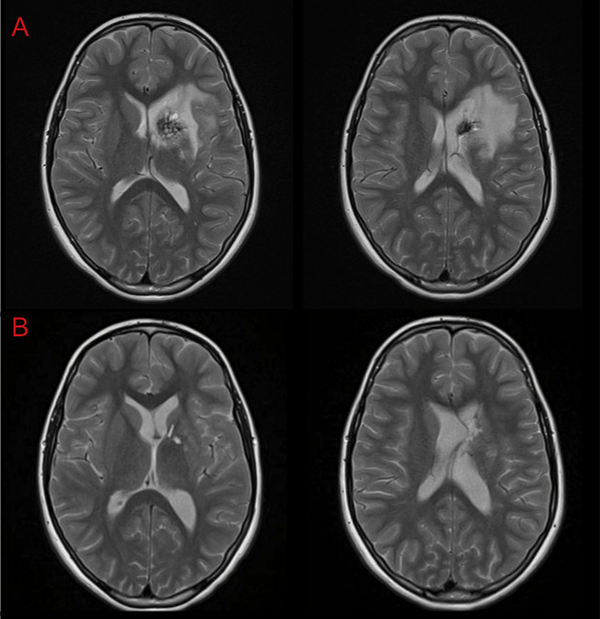

Otra vía considerada fue el abordaje transfrontal mediante el uso de la técnica “tubular”7 o mediante corticotomía; ambas permitirían acceder al Cavernoma en forma directa pero con la posibilidad de no abarcarlo en su totalidad o incidir inadvertidamente las fibras de la CI. Aunque la elocuencia del tejido a nivel frontal es menor y toleraría mejor las maniobras de retracción necesarias, consideramos que ese corredor quirúrgico también sería estrecho. Nos inclinamos por la vía interhemisférica contralateral por considerar que el sangrado previo según se evidencia en la RMI (Figura 6) había delineado una vía de acceso que evitaría realizar una nueva incisión sobre el tejido sano interpuesto.

Figura 6: RMI A- Preoperatoria. B- Control posoperatorio a las 24hs.